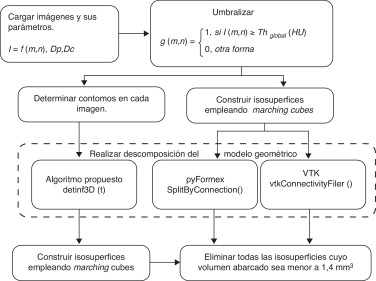

Se desarrollaron 3 aplicaciones (fig. 2 ) para la obtención de estructuras óseas: la primera basada en el algoritmo propuesto en 2.5 y las restantes empleando VTK y pyFormex, respectivamente.

|

|

|

Figura 2. Algoritmos empleados para la definición de estructuras óseas. |

Cada conjunto de imágenes fue procesado indistintamente por las 3 variaciones y los dominios geométricos de las estructuras anatómicas obtenidos fueron comparados empleando como métricas la cantidad de huesos delimitados correctamente y el tiempo de procesamiento.